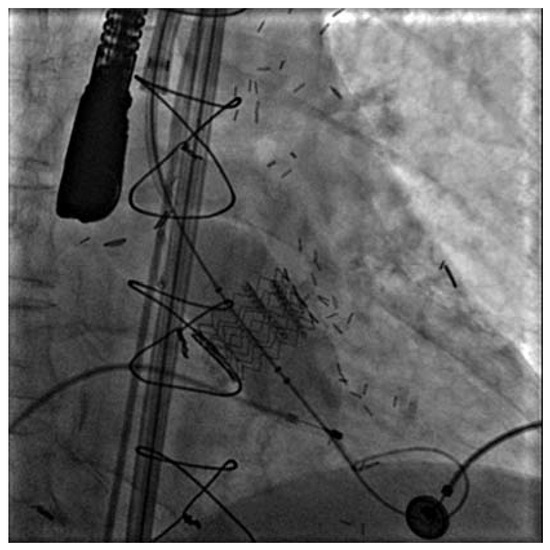

Nichtkoronare Eingriffe—Neue Horizonte in der Kardiologie und Herz-Gefäss-Chirurgie

by Thomas F. Lüscher, Lukas Altwegg and M. Roffi

Cardiovasc. Med. 2007, 10(7), 229; https://doi.org/10.4414/cvm.2007.01259 - 24 Aug 2007

Die koronare Herzkrankheit ist das mit Abstand bedeutendste Krankheitsbild der kardiovaskulären Medizin [...] Full article

Show Figures

Figure 1